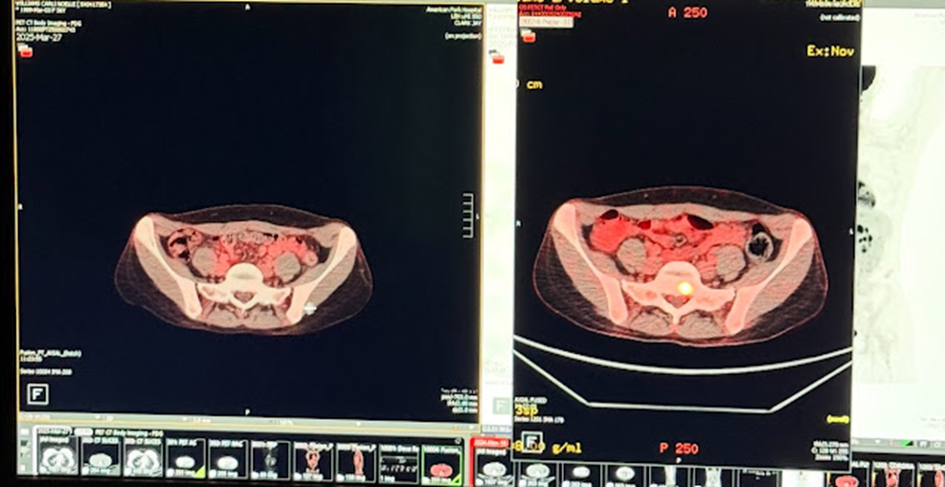

WYNIKI po 2,5 miesiącach: – Marker krwi nowotworowej CA15.3 spadł z 50,1 do 26,9 – SIGNATERA (krążące DNA nowotworowe) spadło z 5,1 do 0,07 (!!) – Skan PET wykazał zmniejszoną aktywność metaboliczną we wszystkich przerzutach kostnych i wszystkich przerzutach do węzłów chłonnych. Jedynym problemem, na jaki natrafiliśmy, był MRI, który wykazał pewne „większe” zmiany kostne, które prawie na pewno były obszarami gojenia się kości w dotychczas niewidocznych obszarach raka. Jest to jedna z głównych zalet PET/CT w porównaniu z MRI lub CT – jest w stanie zidentyfikować „wygojone przerzuty kostne”, które wyglądają na „większe” z powodu stwardnienia (gojenia się kości), ale mają niższą lub żadną aktywność metaboliczną z powodu zabijania komórek nowotworowych.

„Skan po prawej jest z listopada i pokazał raka piersi w stadium IV w kręgosłupie mojej żony. Skan po lewej jest z wczoraj i pokazuje „Brak dowodów choroby”. Przestrzeganie każdego protokołu onkologa doprowadziło moją żonę do wyczerpania i myśli samobójczych (a rak i tak powrócił), więc zaczęliśmy robić własne badania i znaleźliśmy protokół, który wydawał nam się dobry i jak dotąd działa. Lekarz interpretujący skan PET był zszokowany, że rak się zmniejszył, biorąc pod uwagę fakt, że obecnie nie stosuje żadnego konwencjonalnego protokołu chemioterapii”.